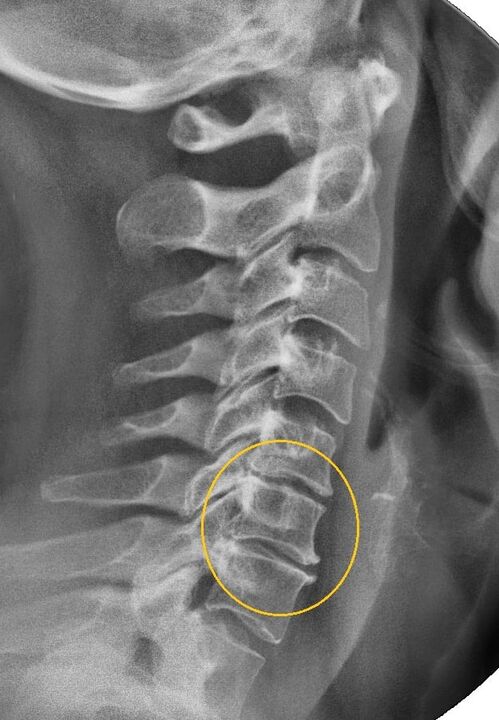

The most informative diagnostic procedure is x-ray.1st degree pathologies correspond to the 1st or 2nd radiological stage.The resulting images display typical signs of the disease.

| Radiographic stages of 1st degree cervical osteochondrosis | Characteristic signs |

|---|---|

| Phase 1 | Small changes in the curvature of the spine in the cervical region, affecting one or more segments |

| Phase 2 | Slight thickening of the intervertebral discs, deformation of the uncinate processes, straightening of the lordosis, slight growths of the bone structures |